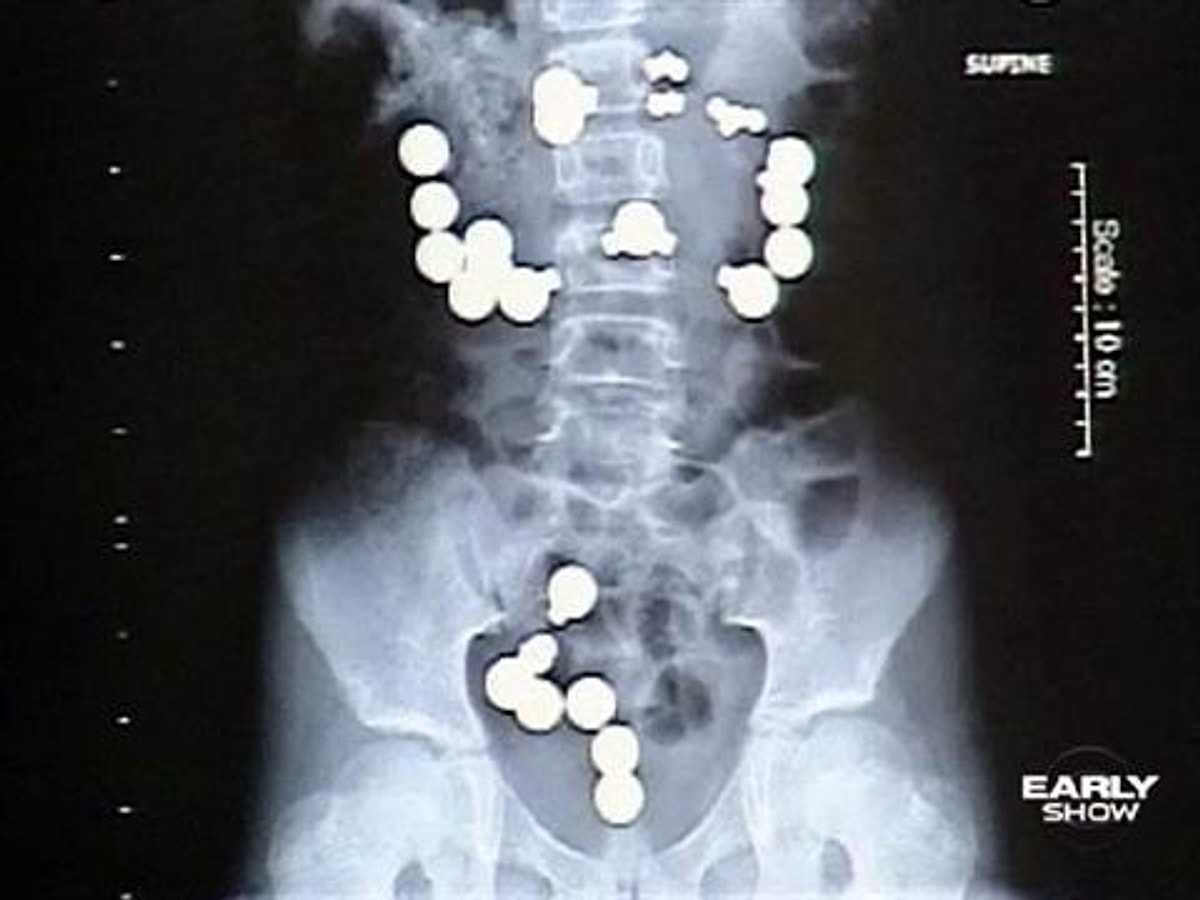

Признаки что ребенок что то проглотил

Признаки что ребенок что то проглотил 108 фотографий